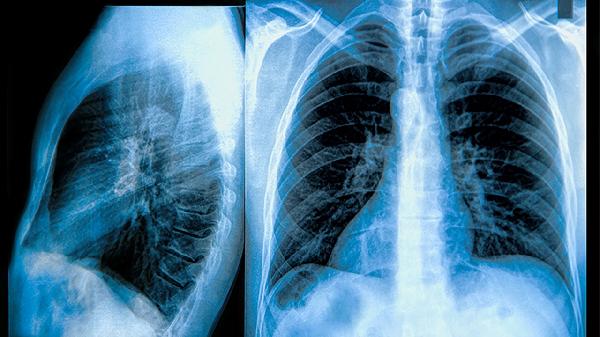

慢阻肺后期症状可通过氧疗支持、药物治疗、呼吸康复训练、心理干预及营养管理缓解,通常与气道阻塞加重、肺部感染反复、呼吸肌疲劳等因素相关。